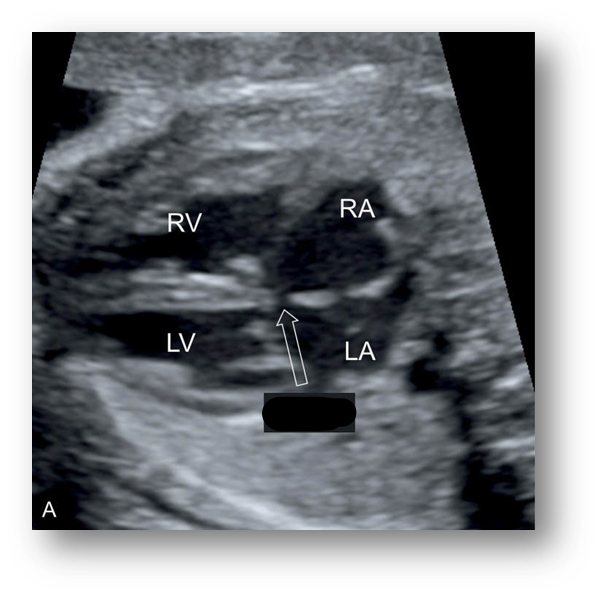

Ultrasound findings of Tricuspid Atresia.

Large, left ventricles

Small, underdeveloped right ventricle

Echogenic tricuspid annulus & no valvular movement

Use color doppler

Tricuspid Atresia